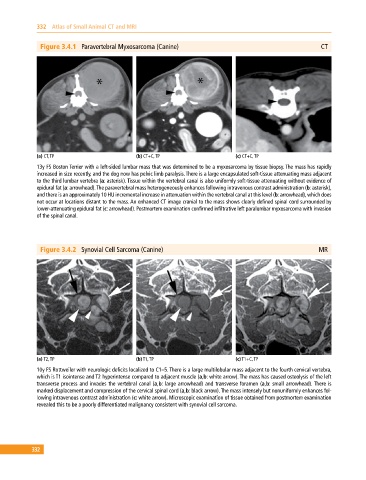

Figure 3.4.1 Paravertebral Myxosarcoma (Canine) CT

(a) CT, TP (b) CT+C, TP (c) CT+C, TP

13y FS Boston Terrier with a left‐sided lumbar mass that was determined to be a myxosarcoma by tissue biopsy. The mass has rapidly

increased in size recently, and the dog now has pelvic limb paralysis. There is a large encapsulated soft‐tissue attenuating mass adjacent

to the third lumbar vertebra (a: asterisk). Tissue within the vertebral canal is also uniformly soft‐tissue attenuating without evidence of

epidural fat (a: arrowhead). The paravertebral mass heterogeneously enhances following intravenous contrast administration (b: asterisk),

and there is an approximately 10 HU incremental increase in attenuation within the vertebral canal at this level (b: arrowhead), which does

not occur at locations distant to the mass. An enhanced CT image cranial to the mass shows clearly defined spinal cord surrounded by

lower‐attenuating epidural fat (c: arrowhead). Postmortem examination confirmed infiltrative left paralumbar myxosarcoma with invasion

of the spinal canal.

Figure 3.4.2 Synovial Cell Sarcoma (Canine) MR

(a) T2, TP (b) T1, TP (c) T1+C, TP

10y FS Rottweiler with neurologic deficits localized to C1–5. There is a large multilobular mass adjacent to the fourth cervical vertebra,

which is T1 isointense and T2 hyperintense compared to adjacent muscle (a,b: white arrow). The mass has caused osteolysis of the left

transverse process and invades the vertebral canal (a,b: large arrowhead) and transverse foramen (a,b: small arrowhead). There is

marked displacement and compression of the cervical spinal cord (a,b: black arrow). The mass intensely but nonuniformly enhances fol

lowing intravenous contrast administration (c: white arrow). Microscopic examination of tissue obtained from postmortem examination

revealed this to be a poorly differentiated malignancy consistent with synovial cell sarcoma.